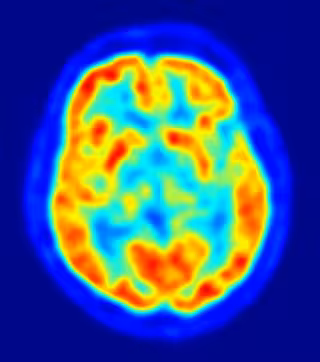

Así, el investigador destaca que la importancia del descubrimiento reside en que durante décadas la parte prefrontal del cerebro fue un "misterio" y se la llegó a considerar "silente". "La comunidad científica llegó a pensar que no tenía ninguna función, debido a que muchos pacientes que habían sufrido lesiones en el córtex prefrontal mostraban una recuperación asombrosa de sus facultades, como si no hubieran sufrido ningún daño", ha relatado.

La región prefrontal controla la parte más "intrínsecamente humana" del cerebro, relacionada con "la capacidad de comprender el lenguaje hablado, de recordar el pasado o sentir y emocionarnos con esos recuerdos. Afecta a la capacidad de planificar el futuro, o ser animales sociales", detalla el investigador de la UIB.

Esta automática compensación del daño no sucede con la parte occipital (vista) o la parte motora del cerebro, dado que si se produce una lesión en esas regiones el daño es difícilmente reducido.